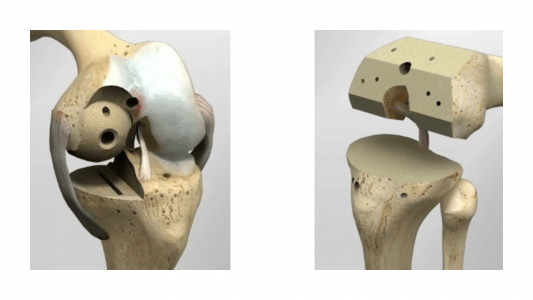

Μια εντελώς διαφορετική και πρωτοπόρα προσέγγιση στην χειρουργική αντιμετώπιση της οστεοαρθρίτιδας του γόνατος, με σημαντικά οφέλη για τον ασθενή, έρχεται να καθιερώσει η Κλινική «Κυανούς Σταυρός-Euromedica» Θεσσαλονίκης. Πρόκειται για την διαμερισματική αρθροπλαστική γόνατος, η οποία, σε αντίθεση με την συνήθη, ολική αρθροπλαστική, εστιάζει στην αντικατάσταση μόνον του φθαρμένου τμήματος της άρθρωσης (Εικόνα 1), χωρίς να θυσιάζονται τα υπόλοιπα υγιή τμήματα του γόνατος (Εικόνα 2).

- Μικρότερης έκτασης οστεοτομίες-κοψίματα (Εικόνα 4),